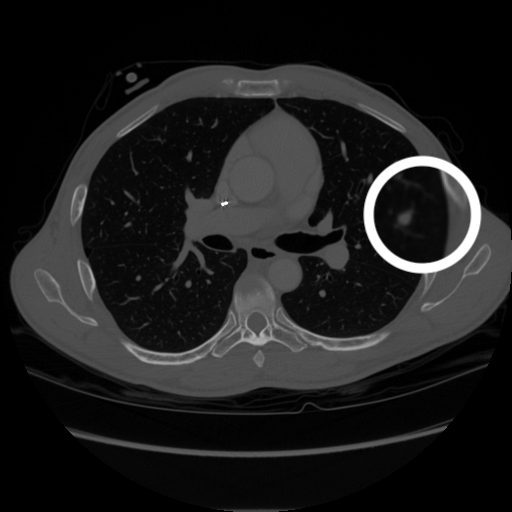

3.1.3 Example 2: data driven reconstruction methods in lung CT screening

There is sufficient evidence that screening for certain tumours using CT images may improve prognosis of cancer survivability (citep \@BBN(Boiselle, 2013)). As mentioned above, in order to gain better image quality with less X-ray dose, many enhanced regularization techniques with integrated machine learning steps have been suggested for CT reconstruction, and in a full reference setting they are commonly evaluated by applying PSNR and SSIM, see e.g. (citep \@BBN(Adler and Öktem, 2018; Hendriksen, Pelt, and Batenburg, 2020; Unal, Ertas, and Yildirim, 2021)). As CT images are generally taken to perform a clinical task, they are not the final step of a medical process but often the initial one. Therefore the definition of what makes a good image heavily depends on the task in hand, and for prognosis related cancer the identification of tumours is of upmost importance.

In on-going research on photon counting detector types and screening procedures for lung cancer (EPSCR grant: EP/W004445/1) an experiment was conducted testing enhanced reconstruction algorithms. Simulations using less than 10% of a clinical X-ray dose were performed to investigate if data-driven methods could sufficiently enhance the images to clearly see the tumours in the lungs while providing very low amount of dosage to the patients. The corresponding data was a CT-dose simulation, using images from the open LIDC-IDRI dataset (citep \@BBN(Armato et al., 2011)) as references, as well as simulated and reconstructed images with in-house software. Figure 3 shows the results of the experiment. We show the reference image used as basis for the simulation, together with five different reconstruction algorithms. The first is an iterative solver, a gradient descend algorithm with TV minimization (citep \@BBN(Sidky et al., 2012)) and (c)-(f) correspond to machine learning methods: FBPConvnet is a denoising algorithm that cleans the bad image (citep \@BBN(Jin et al., 2017)), LPD is an iterative unrolled method that combines traditional solvers with machine learning (citep \@BBN(Adler and Öktem, 2018)), Noise2Inverse is a self-supervised learning method (i.e. does not require ground truth data) (citep \@BBN(Hendriksen et al., 2020)) and ItNet is another iterative unrolled method, the best performing winner of the AAPM DL-Sparse-View CT challenge (citep \@BBN(Genzel, Macdonald, and März, 2021)). ItNet is also judged here as the best result according to PSNR, SSIM and LPIPS.

Figure 3: Reference image (a) and outputs of different reconstruction methods (b)-(f) applied to dose simulated data. PSNR/SSIM/LPIPS are unable to identify the best reconstruction (c), where also the tumour is visualized well.

FR-IQA mismatches

This experiment was performed to evaluate the quality of different kinds of CT reconstruction, and especially the lung tumour detection capabilities thereof. The best result according to the chosen IQA measures is given by ItNet in Figure 3(f), which performs visually poorly. Not only the tumour (zoomed in white circle) is significantly less visible in the reconstruction, but ItNet also produces structures in the lung that are different than the ones in the reference image; it blurs and lengthens much of the soft tissue present in the lungs and it also created structure from noise in some places. Moreover, the image is overly smooth. Comparing the other reconstruction algorithms, it seems that FBPConvnet Figure 3(c) is the one performing best at preserving the shape of the lung nodule, even when the resulting image contains enhanced pixel-level noise.

We can see here that the qualitative findings strongly contradict the numbers provided by the selected measures. The reconstruction of ItNet, Figure 3(f), is outperforming the other reconstructions in regards of the measures, and the qualitative winner FBPConvnet, Figure 3(c), is judged as second worst by the same measures. This experiment suggests that the discussed measures are not a good choice for that kind of CT reconstruction applications and are yielding misleading results.

While pixel-independent random noise may be a worse effect in a natural image than a slightly oversmooth reconstruction, this is not true in CT images, where small structures may disappear if smoothing is promoted against edge preservation. In iterative reconstruction algorithms such choices are explicitly made by choosing the prior appropriately, in data-driven models the researcher has limited control on the type of implicit priors the algorithm learns from the data, i.e. model builders do not know what the algorithms chooses to learn from the ground truth. In these cases appropriate evaluation would therefore be even more important to ensure quality. If this is followed by a blind evaluation using non-appropriate metrics, the promotion of less desirable images can happen, chosen by an implicit assumption on the metric rather than the actual goal of the task.